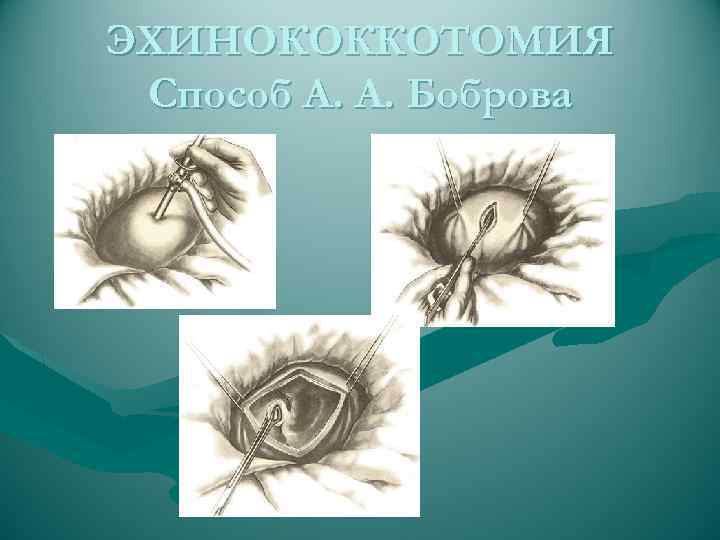

ЭХИНОКОККОТОМИЯ Способ А. А. Боброва

ЭХИНОКОККОТОМИЯ Способ А. А. Боброва

ЭХИНОКОККОТОМИЯ Способ А. А. Боброва

ЭХИНОКОККОТОМИЯ Способ А. А. Боброва